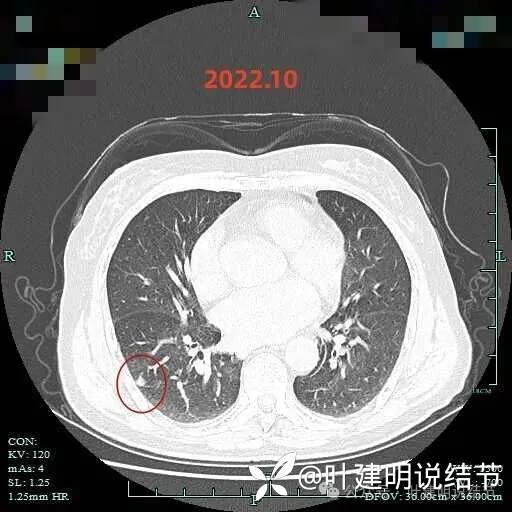

2022年5月右下病灶密度好像更高了,形态也略有变化,边上有微小血管,当然此时层厚是1.25毫米的,较之前薄。

病灶出现,有磨玻璃成分,有血管进入与穿行,血管略有增粗。

混合密度,实性成分明显,微小血管进入明显,整体轮廓清楚,瘤肺边界清楚。

边缘有少许毛刺,实性部分密度较高,牵拉胸膜,边缘少许磨玻璃成分。

边缘区域有磨玻璃成分,实性部分密度主,紧贴胸膜。

边缘淡磨,血管走向病灶。